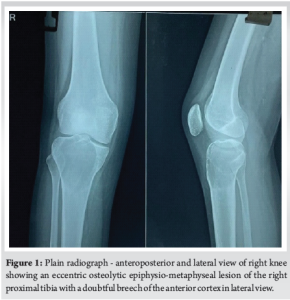

A 22-year-old girl presented with complaints of pain and swelling over her right knee for the past 5 months. The patient also complains of difficulty in squatting. No history of trauma or any other systemic illness. On clinical examination of her right knee, swelling of size 3 × 2 cm is present over the proximal one-third of the anterior aspect of the leg. No local warmth. No signs of inflammation. Tenderness is present over the proximal one-third of the tibia. The range of motion (ROM) of her right knee was 0–80° (further painful). Distal pulses were felt. Sensations were intact. Laboratory tests showed mildly elevated C-reactive protein to 2.1 mg/dL and erythrocyte sedimentation rate of 8. Plain radiograph of the right knee (Fig. 1) showed an eccentric osteolytic epiphysio-metaphyseal lesion of the right proximal tibia with a doubtful breach of the anterior cortex.